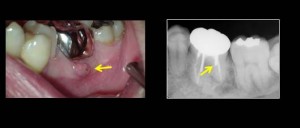

そして、お口の中はこのように歯肉が腫れ、押すと膿が出てきます。原因は・・・・。

レントゲン写真の矢印の所が怪しい・・・。

金属の心棒が3本歯の中にあるのですが、矢印の部分だけが、神経管の方向とちょっと違う。ここに原因のひとつがありそうだなと。